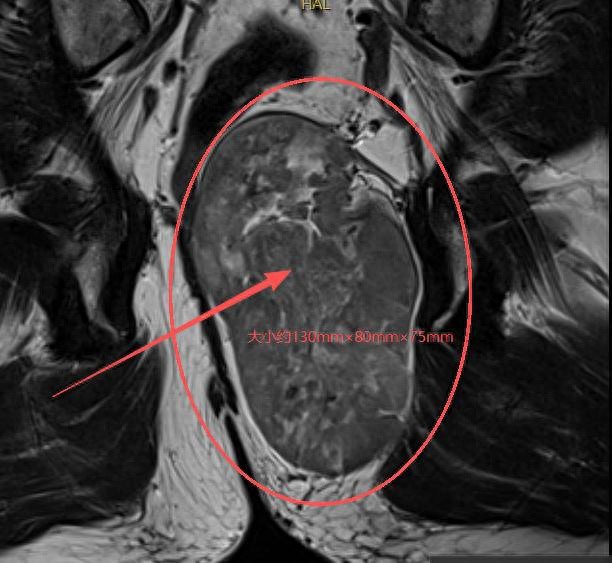

在南京市中医院,核磁检查显示:李先生直肠后方尾骨前方见不均质肿块影,大小约130mm×80mm×75mm(上下径×前后径×左右径),直肠及前列腺均受压移位。

南京市中医院肛肠科团队主任中医师樊志敏教授解释,该肿瘤体积巨大,肿瘤压迫直肠导致患者出现大便难解等不适症状,且肿瘤所处位置极为特殊,深居于骶骨与直肠之间的极狭窄间隙,边界不清,与骶骨、直肠、前列腺紧密相连,周围密布支配排便、性功能的神经丛及关键血管,稍有不慎,便可能引发大出血、神经损伤、直肠损伤、肠瘘、前列腺损伤出血等严重后遗症,手术难度和风险堪称临床难题。“正因如此,李先生几经周折,最终就诊于我院。”樊志敏教授说。